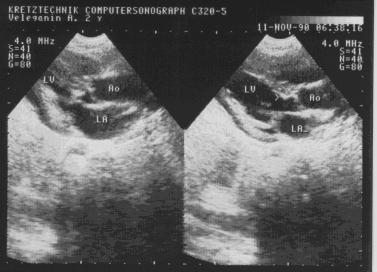

Подклапанный дискретный фибромышечный стеноз аорты.

Рис.98.

Подклапанный

дискретный

фибромышечный

стеноз аорты.

1. Визуализация туннельного сужения выходного тракта левого желудочка за счет фибромышечного кольца (рис.97-98).